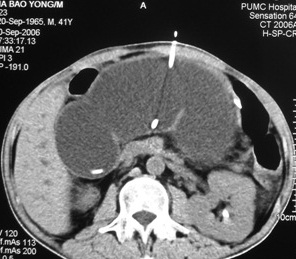

病例简介:男性,胰头癌Whipple(胰十二指肠切除术)术后6个月,腹胀疼,黄疸,发烧,腹部可扪及一包块。化验:TBil 20mg,DBil 15mg,wbc 14000。

![]() ![]() CT显示腹部孤立性肠管扩张,CT引导下扩张肠管经皮空场造瘘。 ![]() PET及PET/CT显示右肾前方高代谢区,提示肿瘤复发

经皮肠造瘘10天后显示Whipple术后的输入袢狭窄

术后病人症状缓解,TBil 2mg ,wbc 8000